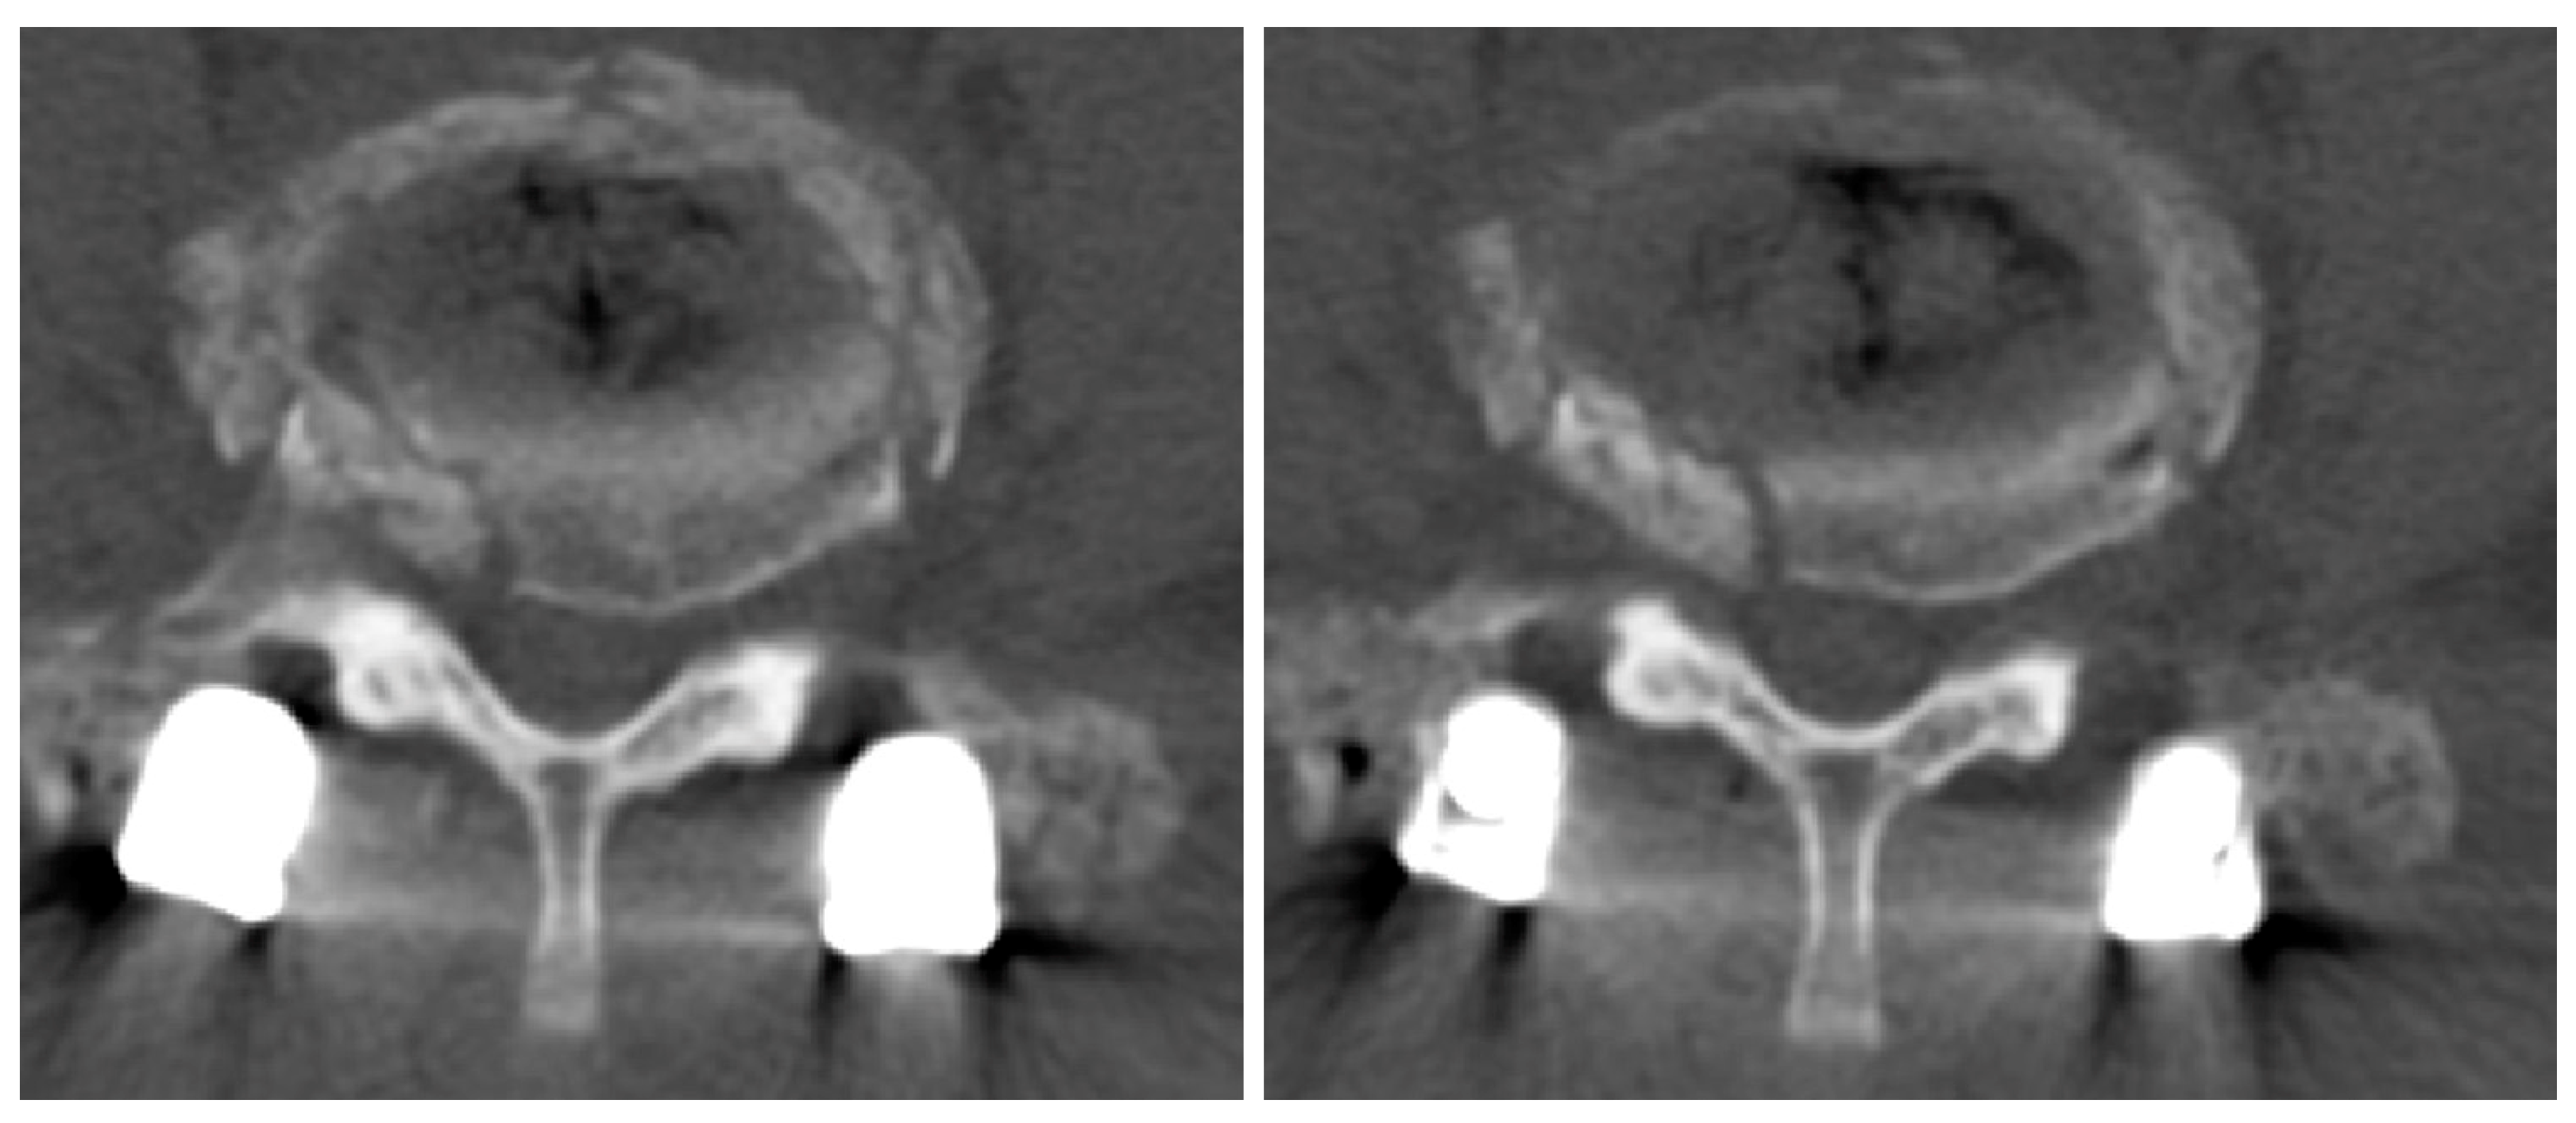

2.1. Case 1

2.2. Case 2